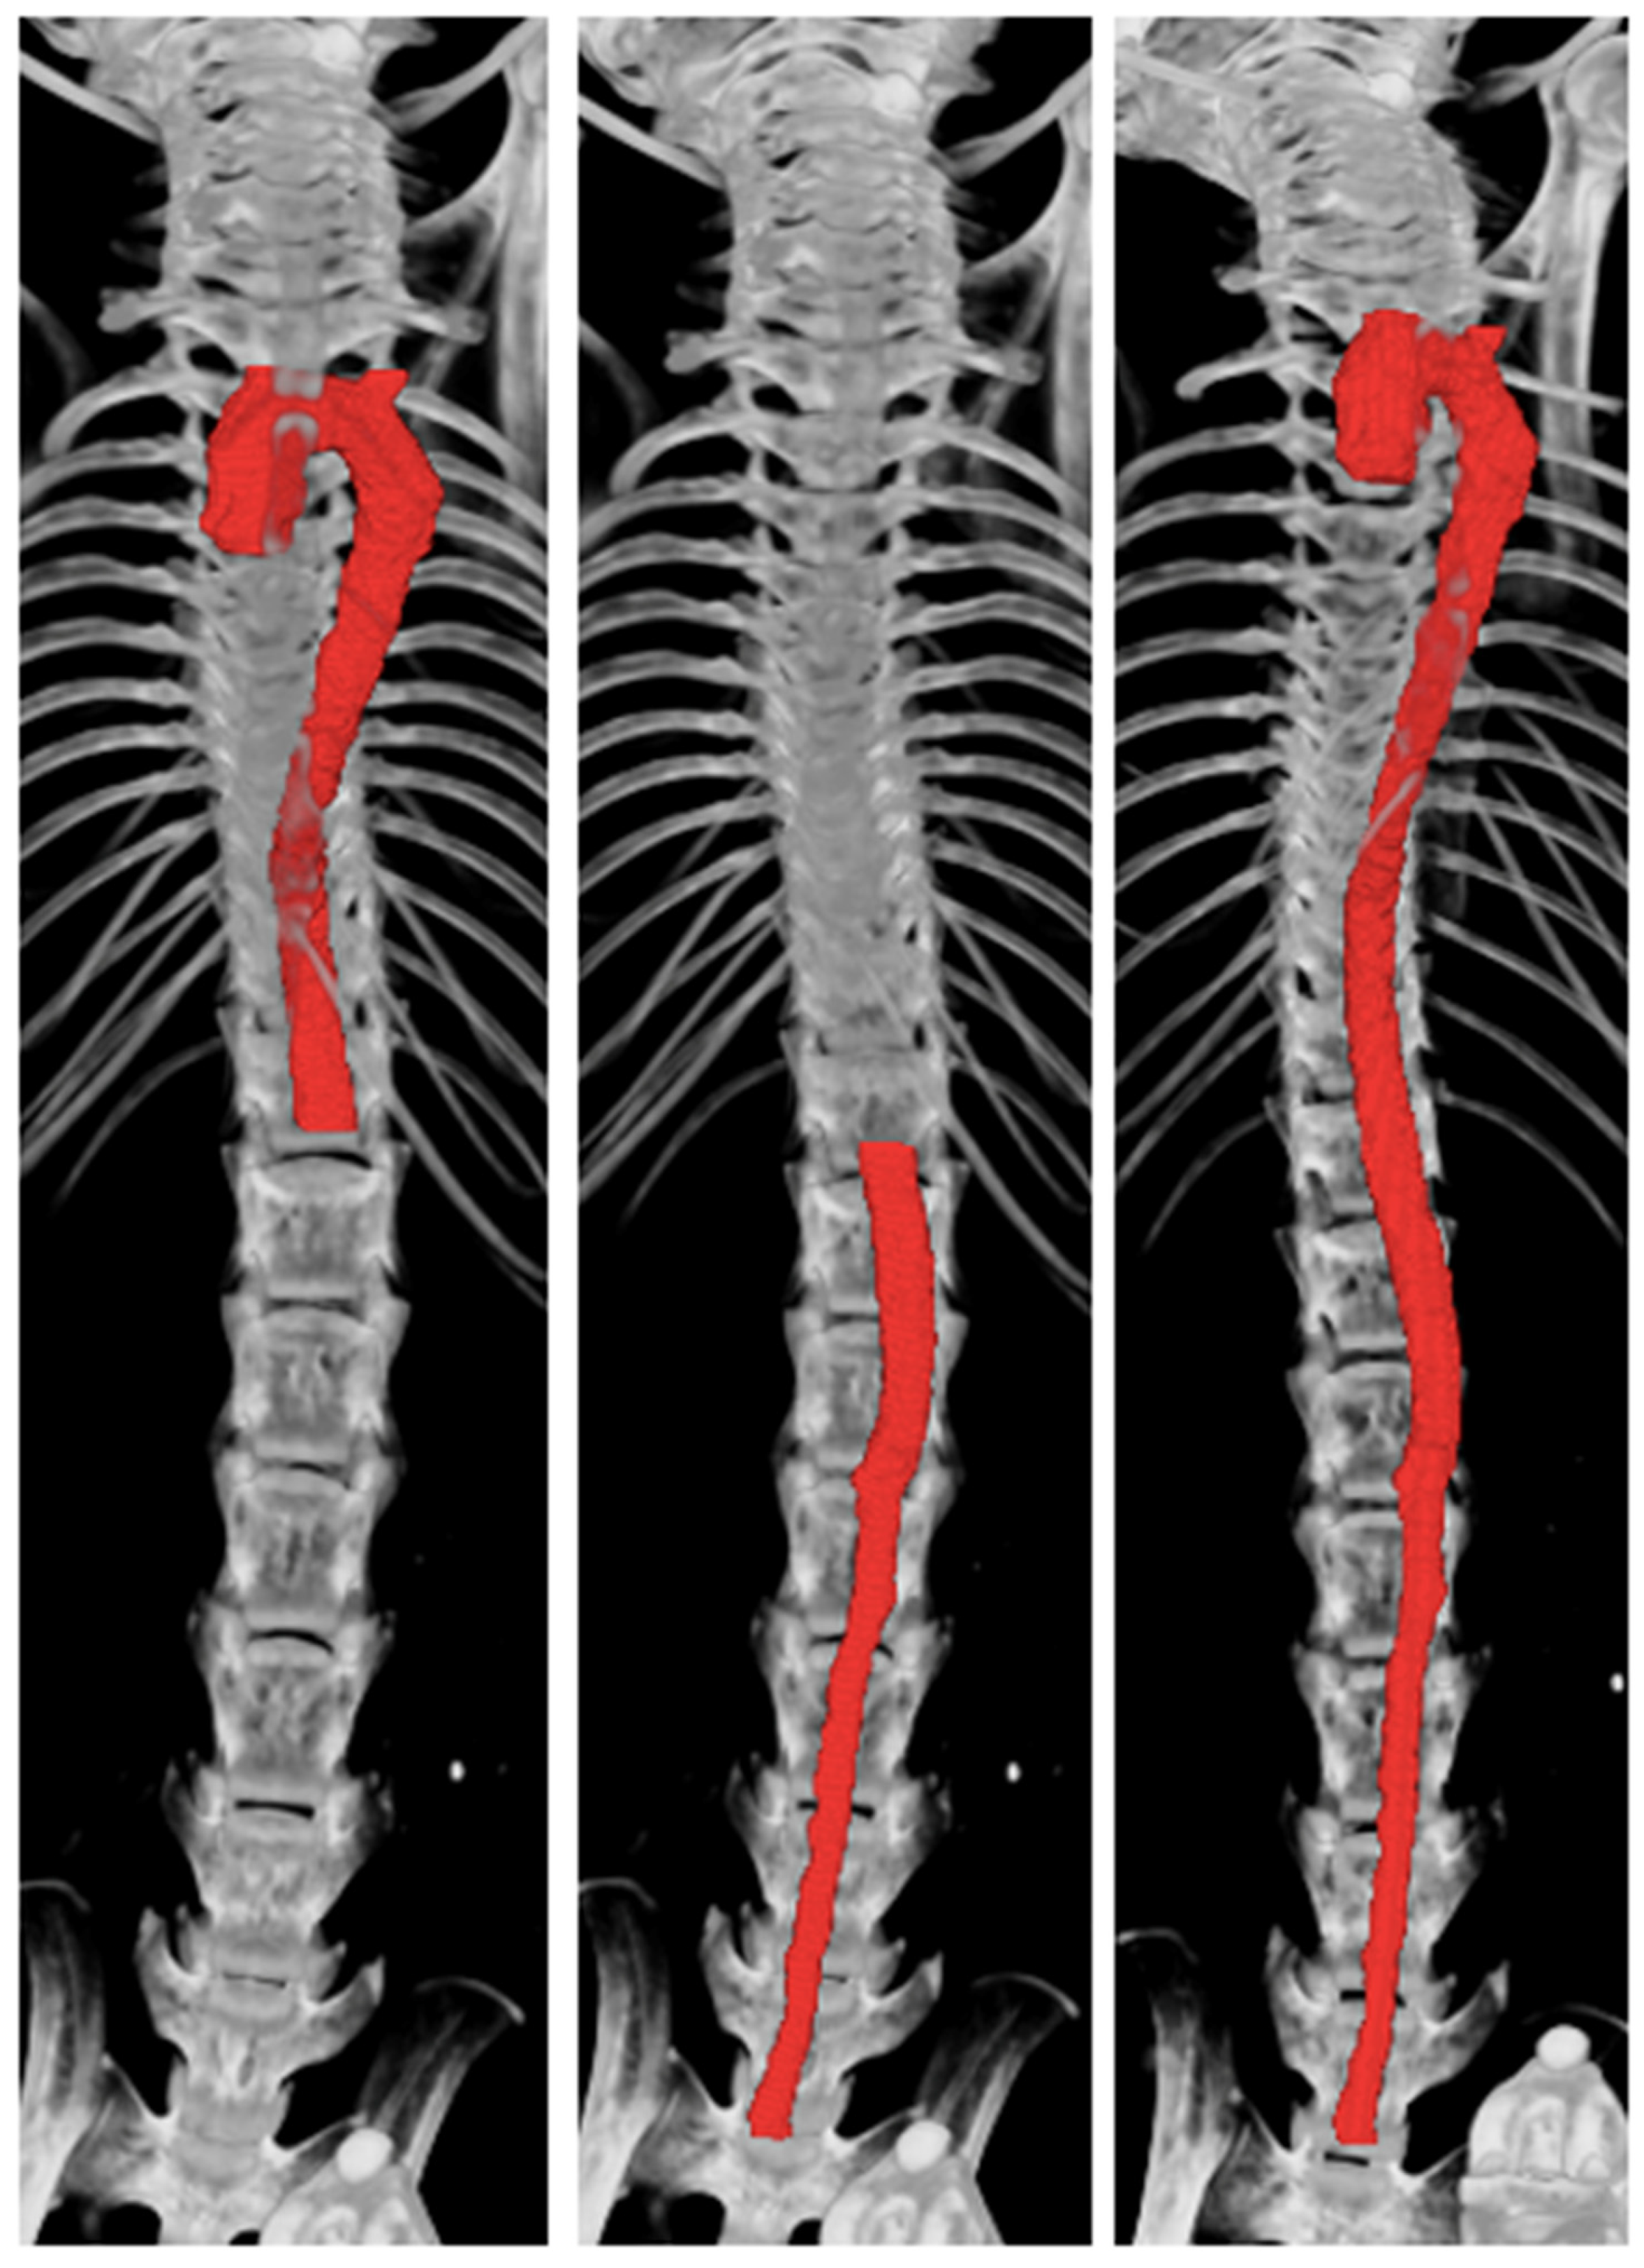

Two independent observers generated the 3D volumes of the aorta from the raw μCT images from five mice. Examples of μCT image reconstruction are shown in Figure 1.

Figure 1.

Micro-computed tomography (μCT) reconstruction of the thoracic, abdominal, and whole aorta using CTan.